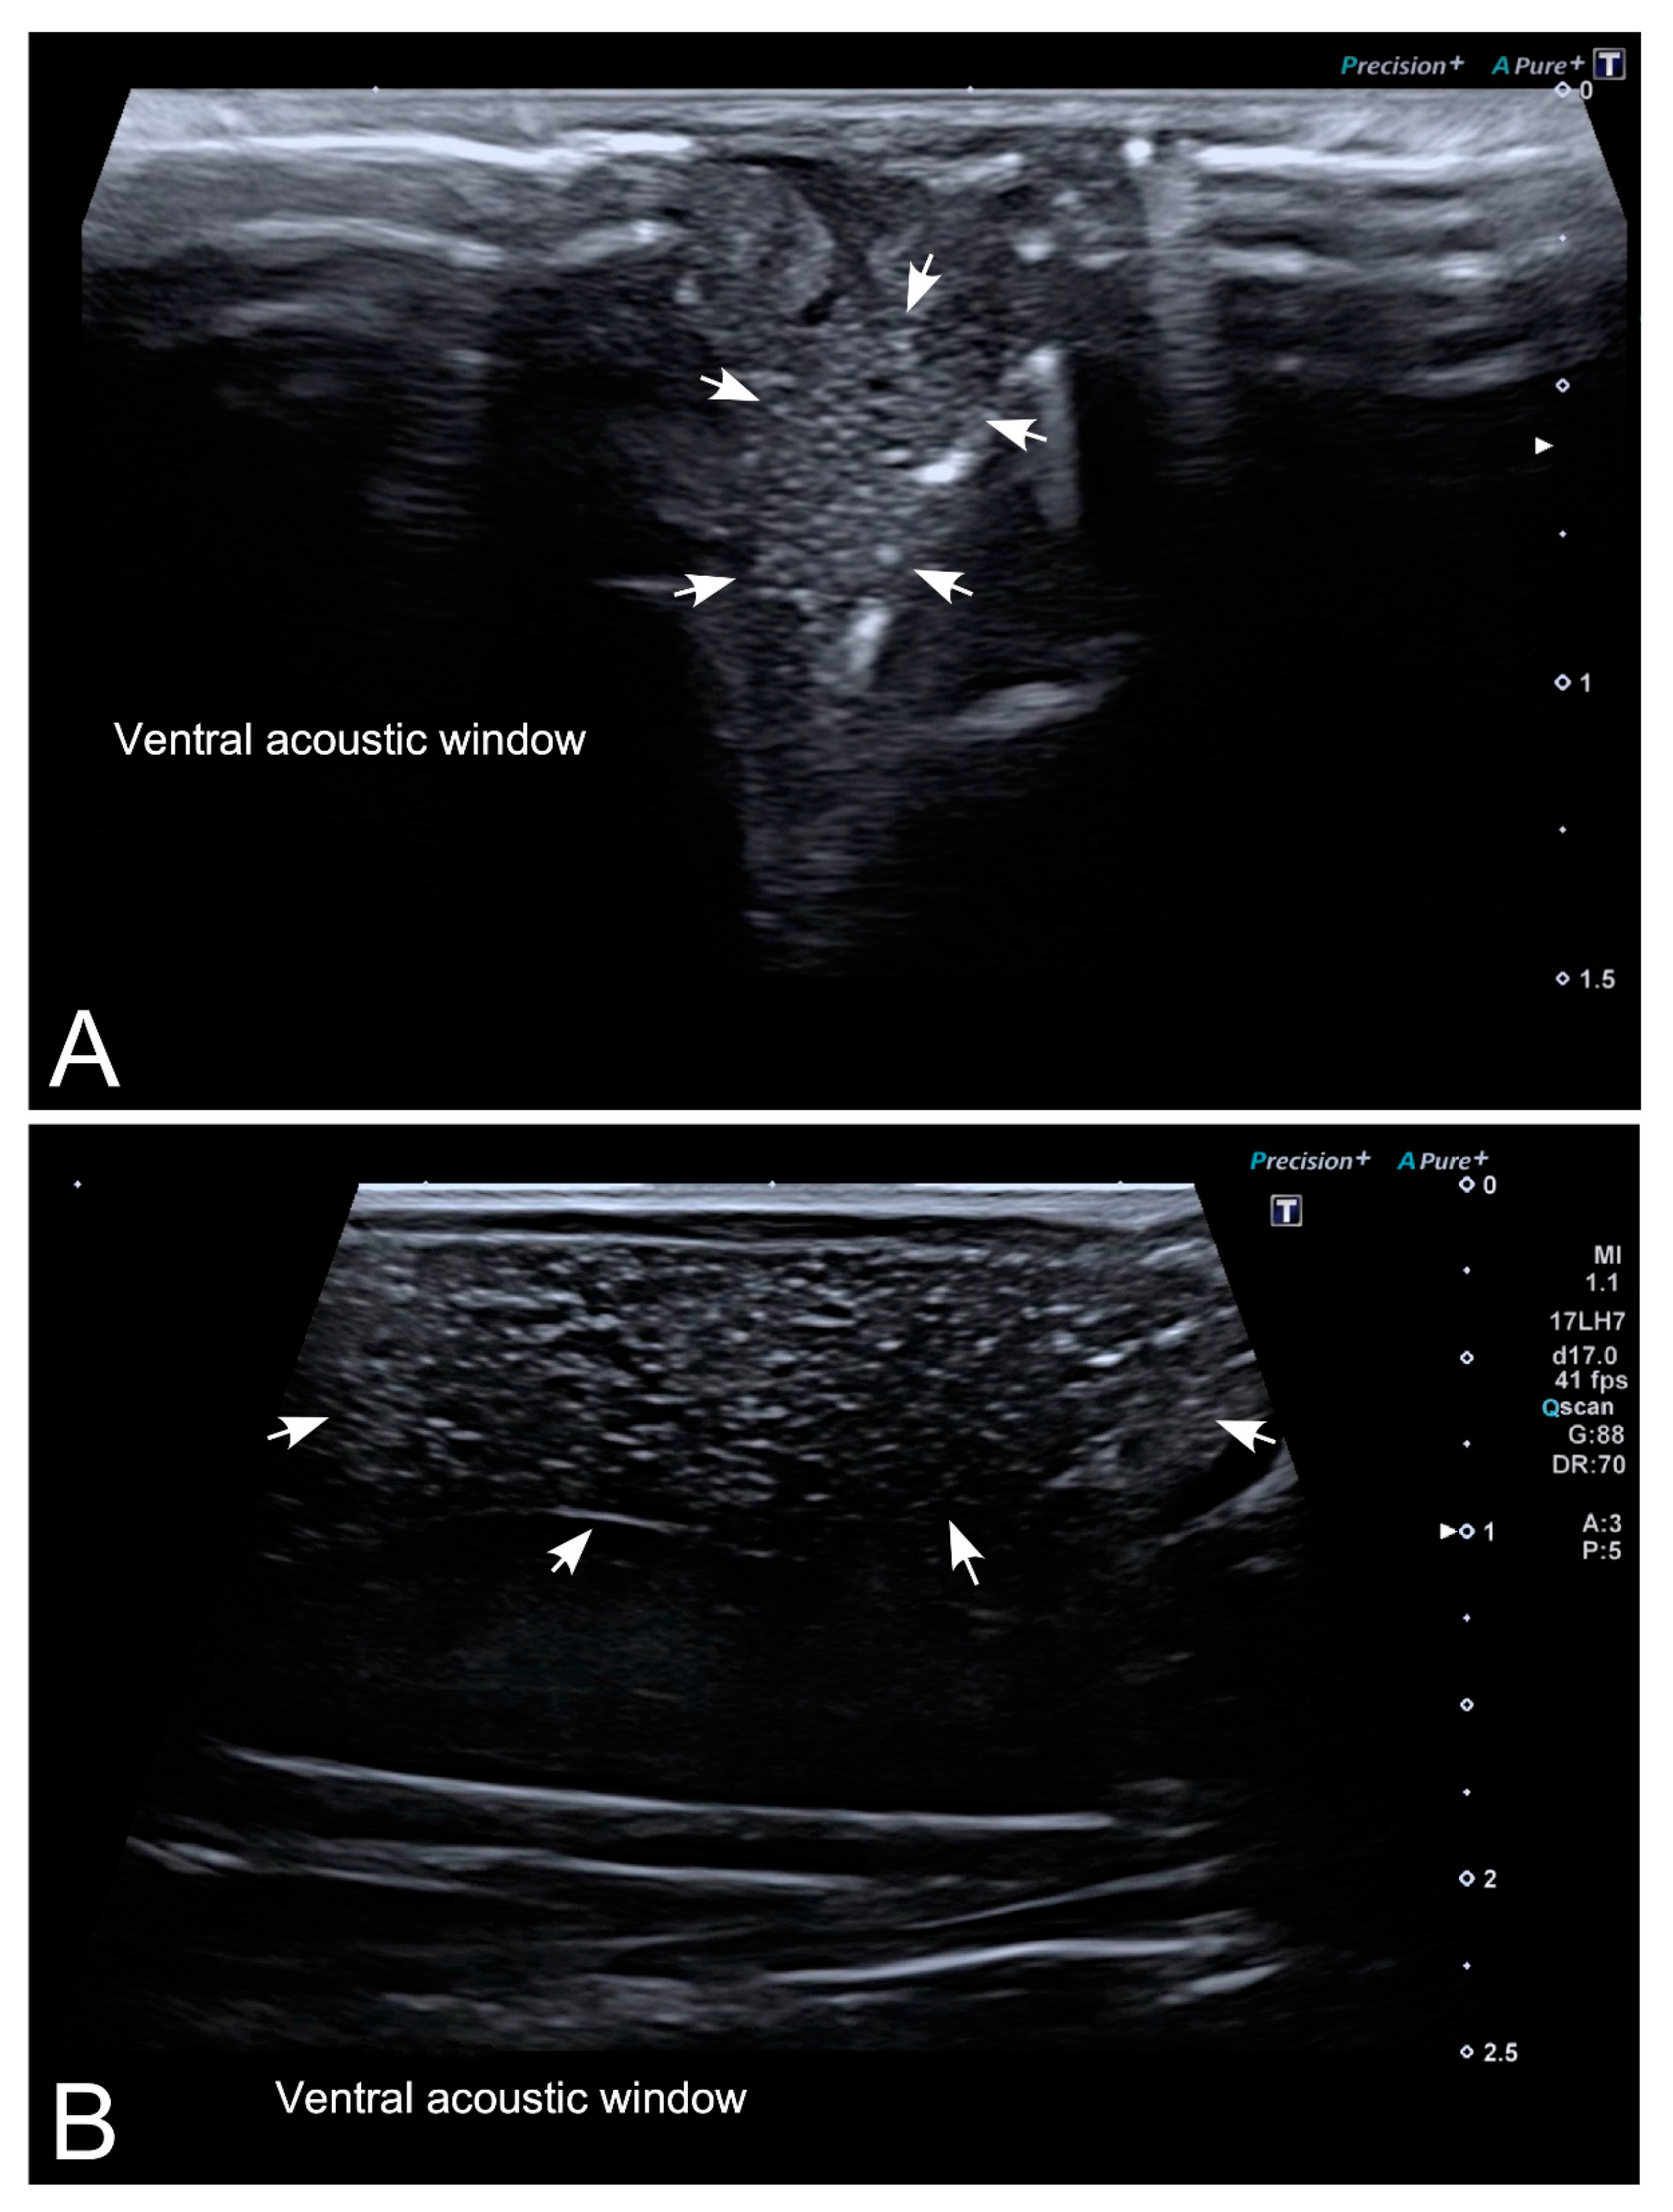

3.2. Ultrasonography